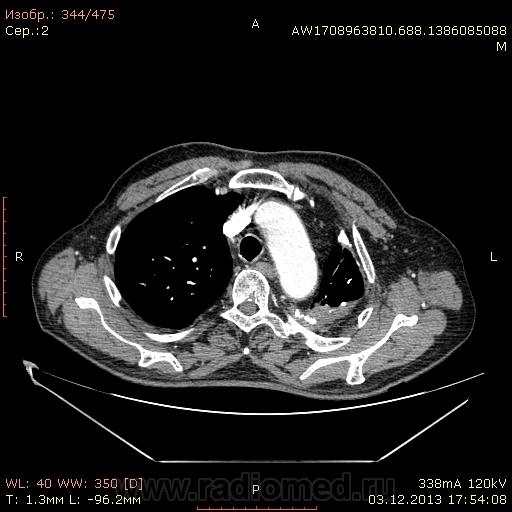

Доброго времени суток уважаемые форумчани! :)Провели исследование КТ грудной клетки с контрастированием, для выявления аневризмы грудного отдела аорты. В результате увидели это:

??? Аневризму честно не вижу (мало опыта в определении аневризм). Тромбоз в бассейне верхней полой вены. В левом легком обызвествленные плевральные шварты? как исход осумкованного плеврита неизвестной давности?

Ребята, вы что, какая жидкость? Чистая известь, посмотрите в костном окне. Отставить натив (в данном случае, хотя для аневризм он обычно нужен). Отставить тромбоз верхней полой вены (потоковые артефакты, не дело вены в артериальную фазу оценивать). Отставить аневризму  аорты, поперчник восходящего отдела на уровне легочного ствола 42мм. А вот легочная гипертензия, здравствуй: поперечник легочного ствола - 37мм, ПЛА - 25мм, ЛЛА - 25мм, НАо - 25-34мм.

Для справки: холестериновые камни имеют плотность менее 100 ед.Н. Имеющаяся хренотень в левом гемитораксе имеет плотность больше костной, до 1500 ед.Н. Вопрос: какая химико-физико-биологическая реакция может способствовать превращению мягинькаво холестерина в термоядерную плевральную лепёшку?)